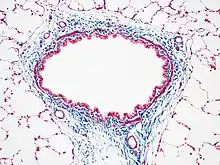

Another common variant is the Masson trichrome & Verhoeff stain, which combines the Masson trichrome stain and Verhoeff's stain.[2] This combination is useful for the examination of blood vessels; the Verhoeff stain highlights elastin (black) and allows one to easily differentiate small arteries (which typically have at least two elastic laminae) and veins (which have one elastic lamina).